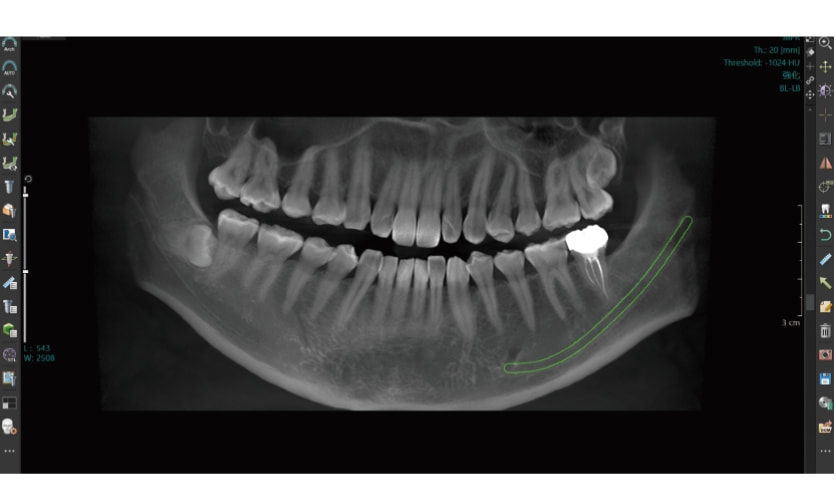

高機能なパノラマ撮影を

鮮明なパノラマ撮影

患者さんの位置付けによる撮り直しのリスクを幅広いフォーカス域を備えることで軽減。

3Dオートフォーカス技術により27mmのフォーカス域から歯列全体にピントの合ったパノラマ画像を簡単に取得できます。

パノラマ画像がボケる理由

患者さんごとに形態が異なる歯列弓を、焦点が合う限られた断層域に正確に合わせるためのノウハウが求められます。

3Dオートフォーカス技術でのフォーカス域

フォーカス域27mmの断層情報により歯列弓形態の個人差や位置付け時のズレにも柔軟に対応し、歯列全体にピントの合った画像が得られます。

3Dオートフォーカスとは?

27mmのフォーカス域内のパノラマ画像を1mm間隔で取得。各パノラマ画像を小さいセルに分割し、その中で最もピントの合った画像だけを自動抽出して、歯列全体にピントが合った1枚のパノラマ画像を再構成します。

パノラマ画像フィルター「P-FLEX」

読影や説明に適した画質に柔軟に変更することができます。複雑な操作を伴わないので、本来の業務に集中いただけます。

高精度距離計測

3D空間上の座標情報に基づき構築された3Dモデルから、平面上で指定された2点間を立体的に計測。

精度の高い距離計測が可能になりました。

パノラマ画像で距離計測が正確でない理由

2D上の距離計測は、歯牙の傾きを考慮した正確な距離計測が不可能でした。

パノラマ3D情報による計測

3Dオートフォーカス技術によるパノラマ3D情報があるため、精度の高い距離計測が可能です。

デンタル画像への切り出し

パノラマ画像からそのままデンタル画像(10枚法、14枚法)への切り出しが可能です。

14枚法によるデンタル撮影テンプレート例